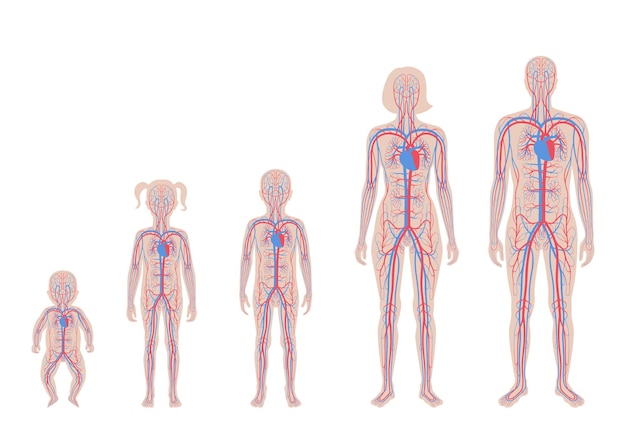

Human Arterial And Venous Circulatory System Anato 21139497

14/11/2025

ร่างกายมนุษย์